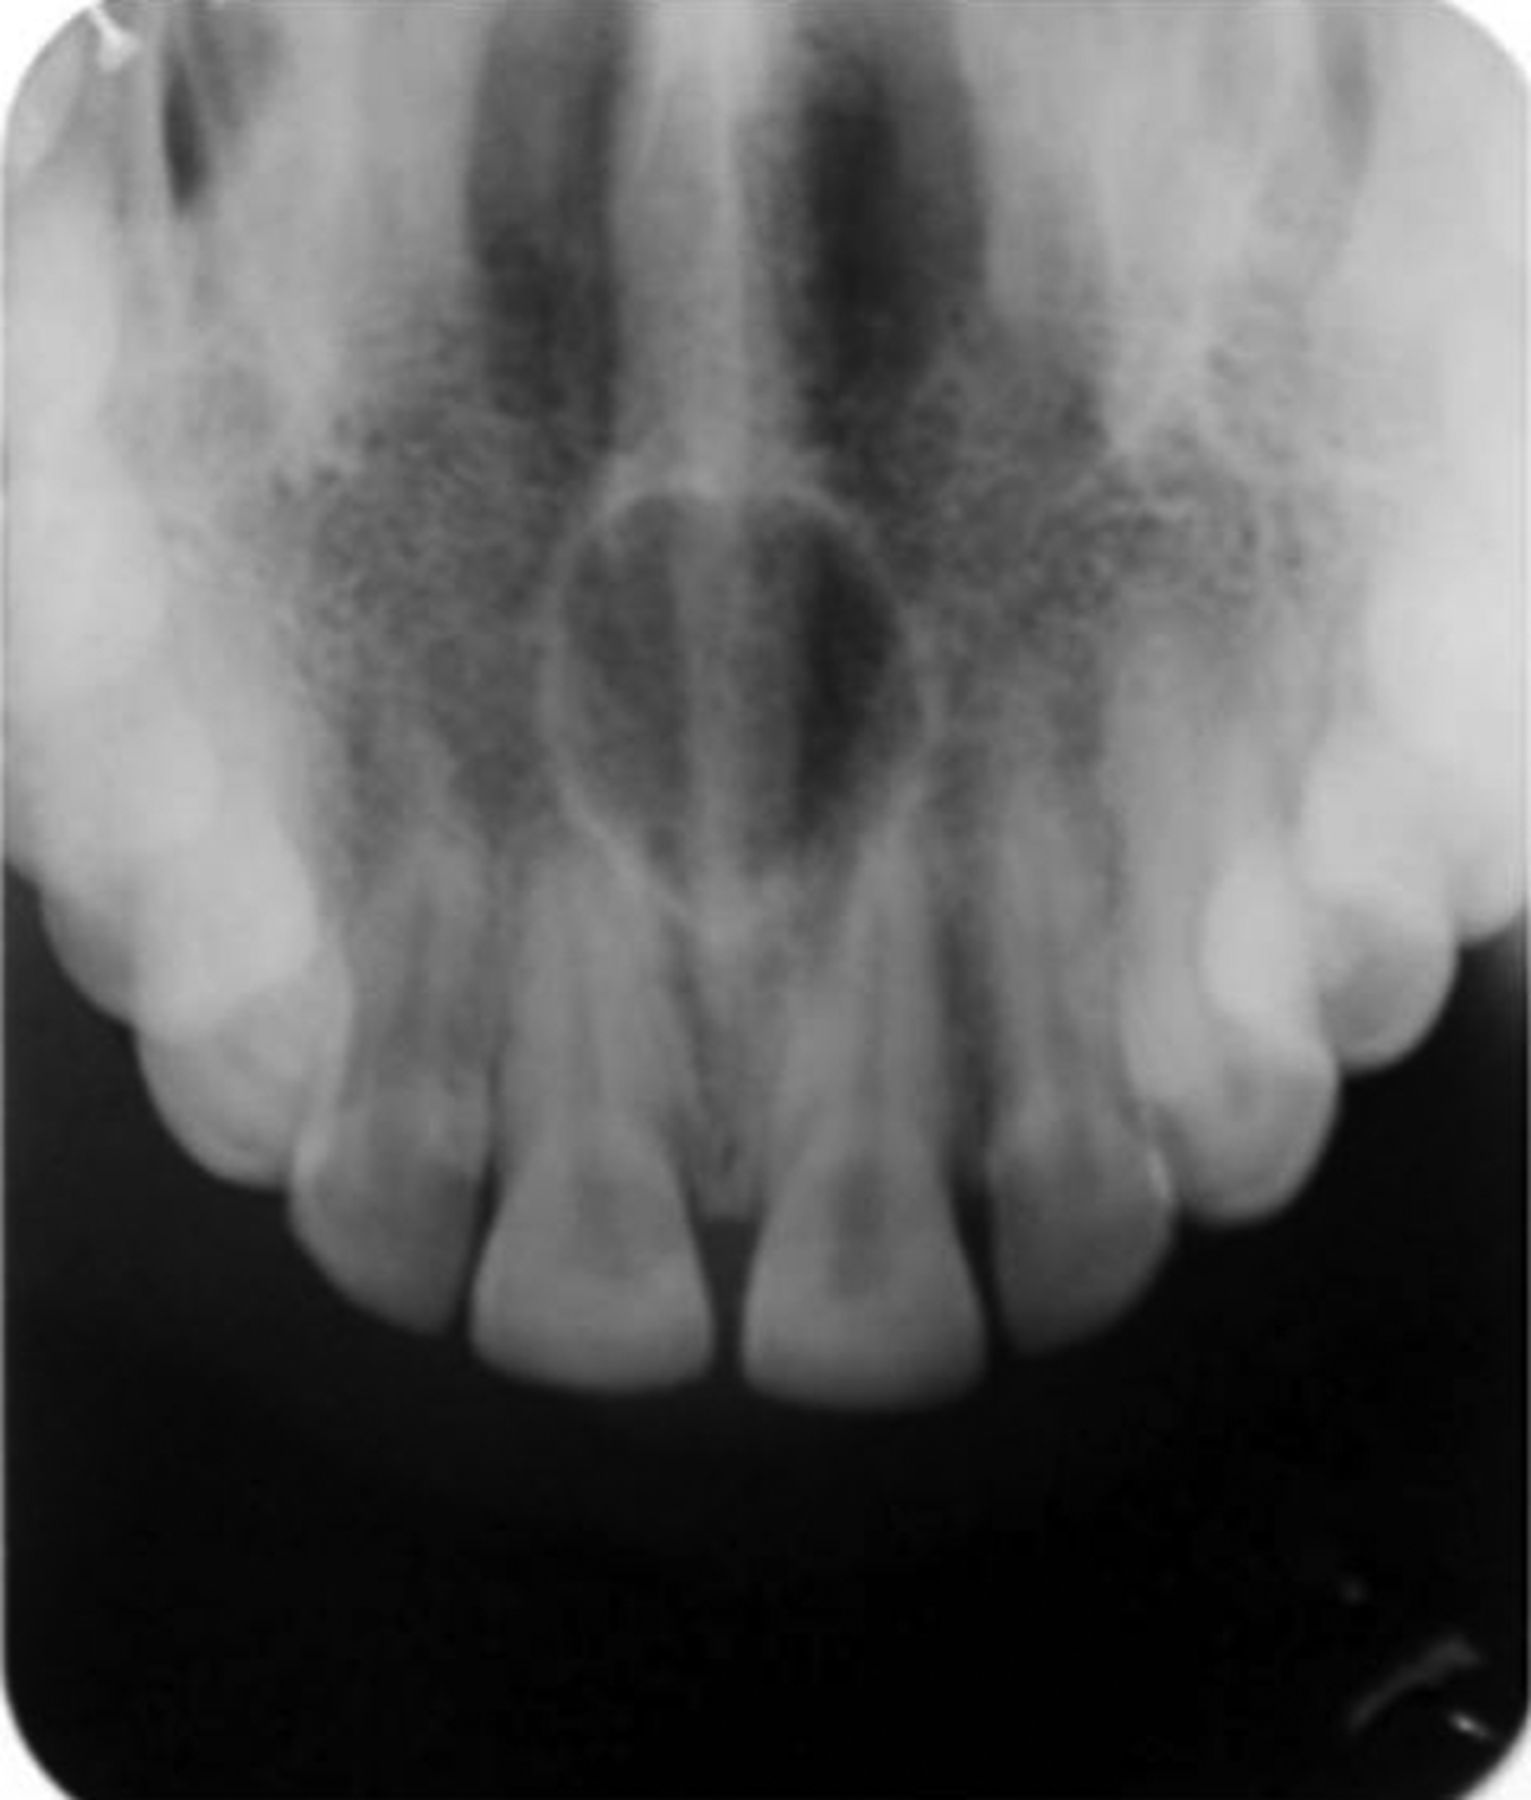

The radiolucency shown by the following radiograph is due to:

Explanation: ***Nasopalatine cyst*** - Classic **midline anterior maxillary** radiolucency located in the **incisive canal/nasopalatine foramen** region, often with a characteristic **heart-shaped** or **inverted pear** appearance. - Most common **non-odontogenic cyst** of the maxilla, arising from embryonic remnants of the **nasopalatine duct**. *Solitary bone cyst* - Typically occurs in the **mandible** (especially posterior region) rather than the anterior maxilla, appearing as a **unilocular radiolucency**. - More common in **younger patients** and often **asymptomatic**, but location doesn't match the midline anterior maxillary presentation. *Ameloblastoma* - Predominantly affects the **posterior mandible** and presents as a **multilocular** ("soap bubble" or "honeycomb") radiolucency. - **Aggressive benign tumor** that causes significant **expansion** and **cortical thinning**, unlike the typical presentation of a midline maxillary radiolucency. *Nasolabial cyst* - **Soft tissue cyst** located in the **nasolabial fold** that typically appears **radiopaque** on conventional radiographs. - Causes **obliteration of the nasolabial fold** and **swelling** rather than presenting as a radiolucency within bone structure.